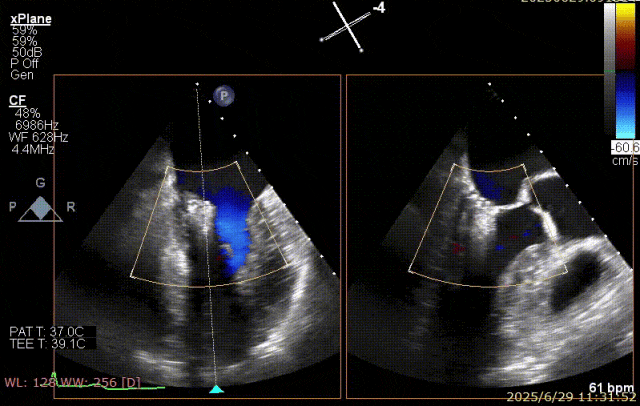

2025 年 6 月 29 日,经过对术前超声和 CT 影像进行深入分析,团队制定了周密手术计划。在麻醉手术中心副护士长刘菊梅的充分术前准备和中国医学科学院阜外医院欧阳文斌教授的指导下,凭借团队的紧密协作和娴熟操作,单纯利用超声影像精确引导,通过导引导管系统经右胸、右房,穿房间隔,建立到达左房通路;经该通路将两枚二尖瓣钳夹成功植入二尖瓣病变部位进行夹持,夹合器位于 3 区及部分 2 区,固定好,运动协调,瓣叶启闭灵活,瓣口轻度反流,二尖瓣平均跨瓣压差 2 mmHg。手术圆满完成。

器械植入后二尖瓣 AP 径约 35 mm,CC 径约 39 mm;夹合器固定好、组织桥稳定,前瓣夹闭后瓣叶长度 25 mm,后瓣夹闭后瓣叶长度 7 mm;二尖瓣开放好,瓣口呈大小双孔,二尖瓣瓣口面积约 2.8 cm²,平均压差 1 mmHg,关闭可,二尖瓣反流明显减轻(从术前反流 4+显著改善至 1+),手术全程无需体外循环支持,无需输血,无需射线全超声引导。患者术后第二日回普通病房,患者恢复良好,术后第五日即出院。